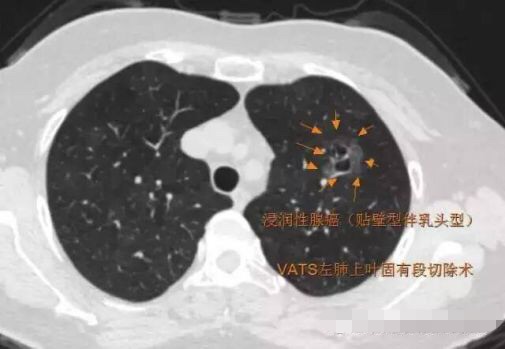

当逐渐长大变坏时,可能会引起实性成分增加,变得不那么纯了,称为混合性GGO;有时,还会出现分叶、毛刺、空泡,胸膜凹陷,血管密集等改变,这时多数已经是恶性了,称为浸润性腺癌。可以进入人类的血管,发生肺内或全身转移。

2014年 首次发现右肺上叶GGO,病灶直径8.3毫米, 2016年复查发现右肺上叶GGO,病灶直径12.4毫米。2年大约生长4毫米,平均1年生长2毫米。2016年手术病理结果:浸润性腺癌。